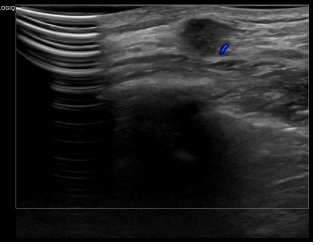

상기환자는 우측유방 만져지는 멍울있어  내원하신 40대초반

여성분으로 의심스러운 우측혹 조직검사 시행해 유방암 진단되었습니다.